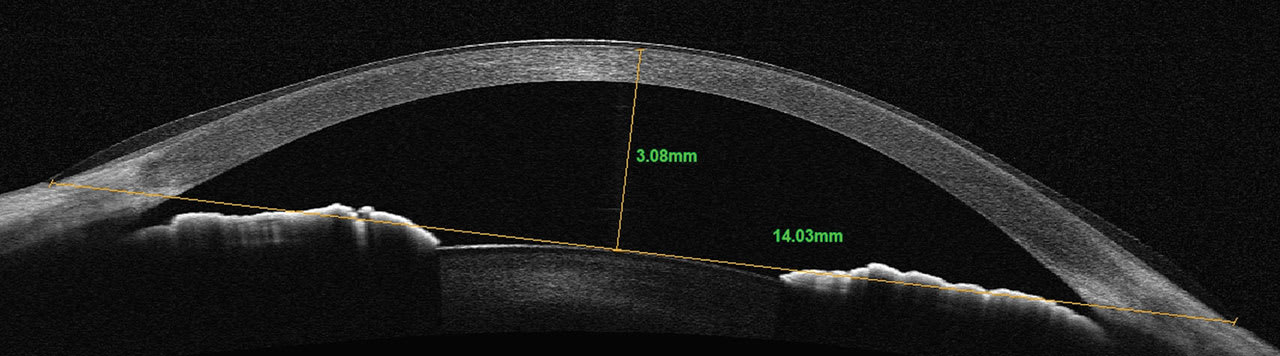

Newer OCT technologies allow for larger horizontal cross-sectional scans of the cornea and anterior segment. It provides the ability to better select the initial diameter of a scleral lens based upon the horizontal visible iris diameter (HVID). Sagittal depth can be measured from the surface of the cornea to any chord length or width of the scan acquired.

A chord length of the diameter of a given lens can be used as a reference point for initial diagnostic lens selection. Once the chord length is determined and placed in the horizontal plane of the scan, measurements from the chord to the anterior surface of the cornea can be made to select the initial diagnostic lens, providing a more customized initial fitting experience. Typically, a sagittal depth 300µm to 400µm greater than the measured sagittal depth would be selected (Figures 3 and 4).